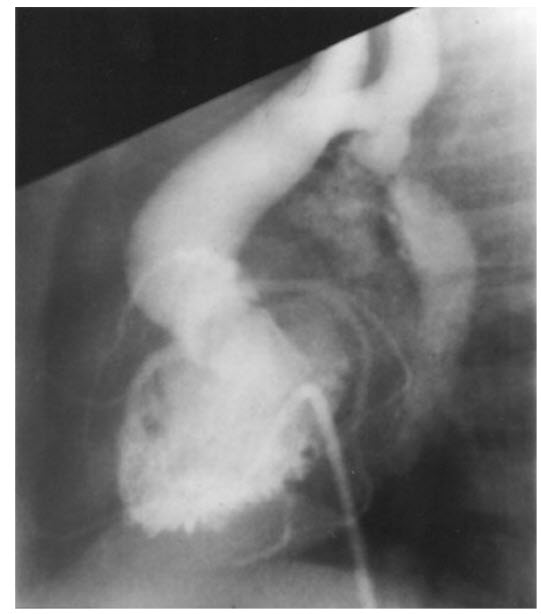

Match the following cardiac catheterization still-frame slide to it's respective diagnosis.

A. Coarctation of the aorta

B. Patent ductus arteriosus (PDA)

C. Hypertrophic cardiomyopathy

D. Pulmonic stenosis

E. Ventricular Septal Disease (VSD)